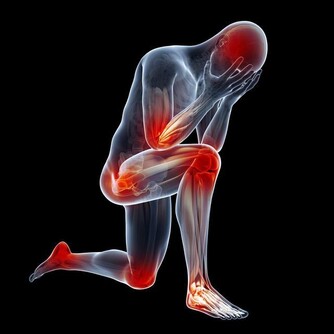

腿腳抽筋可能是因為缺乏維生素D:

說到維生素D,就要說到鈣,這兩種營養成分是非常親密的合作夥伴,

維生素D可以幫助我們機體促進鈣的吸收,

也就是說,在缺鈣的時候,要先補充維生素D,才能更好的幫助我們補鈣,

而且血液中的鈣濃度也不會因為低下,造成腿腳抽筋的現象了。

那我們應該怎麼補充呢?

最直接的辦法就是去外面曬太陽,只要曬到半個小時左右的時間,

就能夠滿足一天中人體對維生素D的需求了,但是這裡要注意的是,不要隔著玻璃或者是隔著實物曬,

這樣太陽光的紫外線才能更好的照射在皮膚上,進而形成人體所需的維生素D。